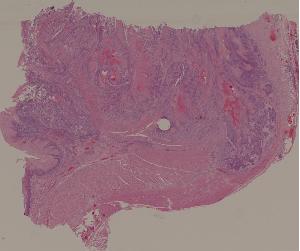

29. Adenocarcinoma of the colon